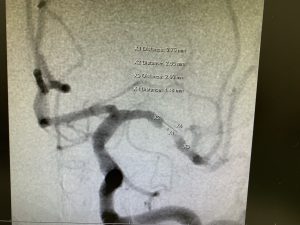

繰り返し再発する頭蓋内中大脳動脈狭窄症に対しwingspanを実施しています。

矢野達也副部長(日本脳血管内手術指導医)の執刀のもと、佐々木院長の指導アシストで実施しています。

治療前中大脳動脈 治療後中大脳動脈

wing span 全景